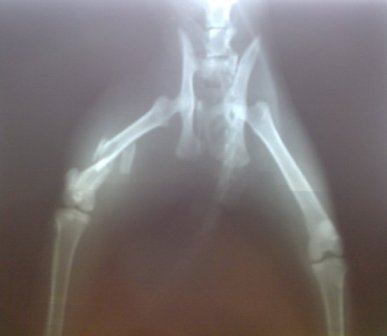

تصاویر جراحی ترمیم استخوان ران شکسته شده گربه (شکستگی چندتایی، 5 قطعه)

تصویر رادیوگراف شکستگی قبل از جراحی